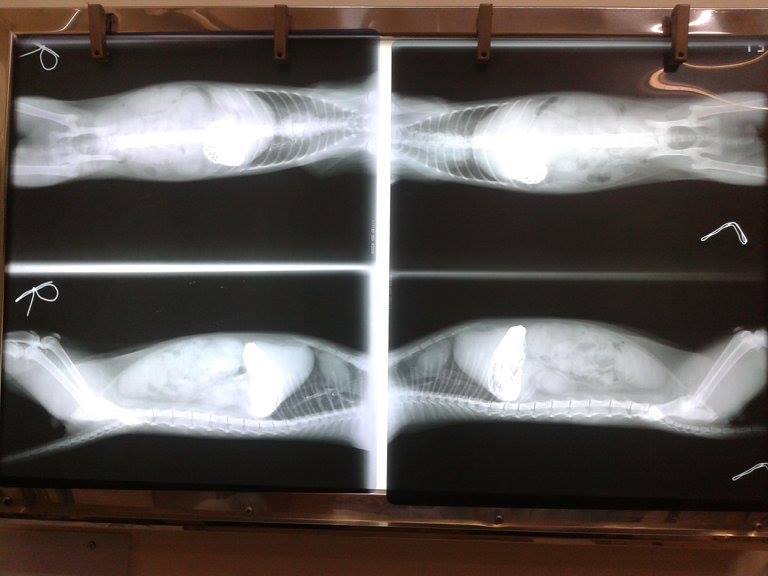

隔天的X光發現,鋇劑無法進入腸胃道,顯示堵塞的很嚴重,立刻安排手術開刀。現在回想著,他一定非常的不舒服且不知道忍耐多久了。

手術後,醫師說腸道已經開始潰爛,並有超過一半已經壞死,壞死的部分只能割除,只能盡最大的能力去救治了。